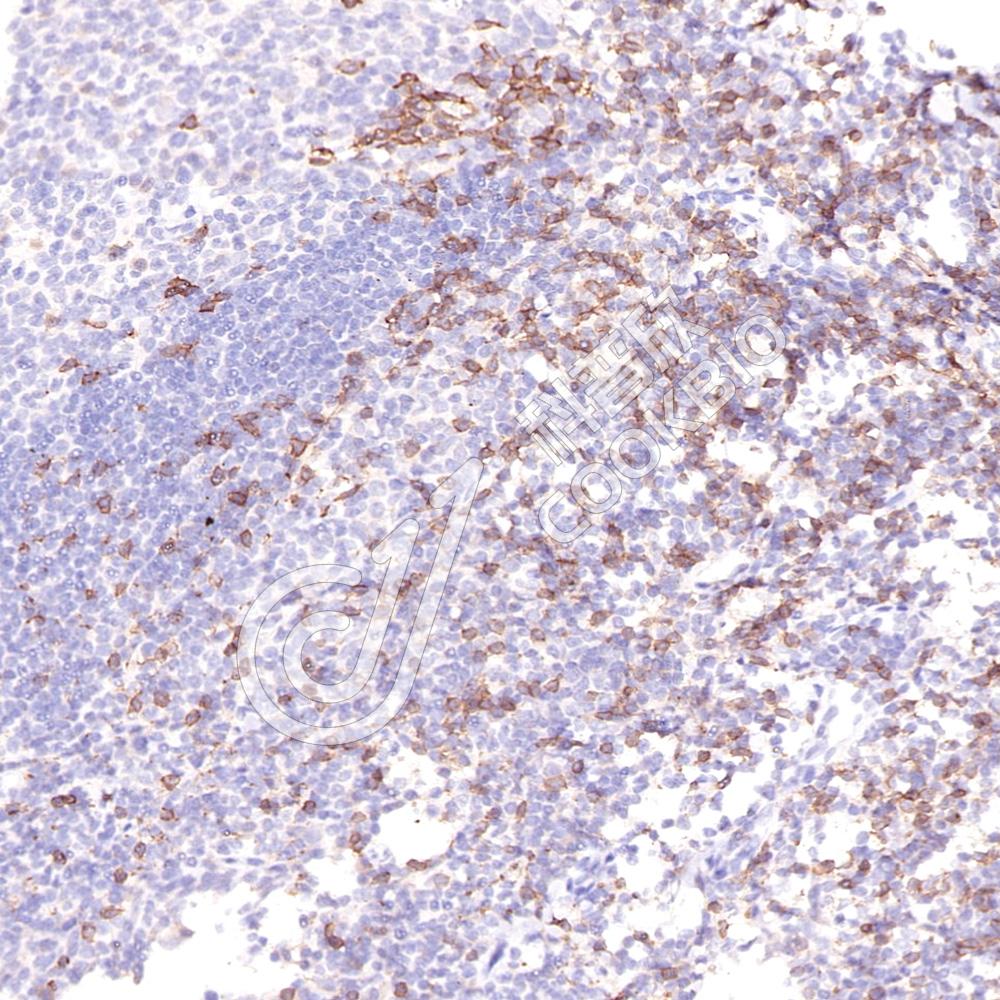

IHC检测CD8 alpha蛋白(货号 K1342369).

样品: 人扁桃体, 4%多聚甲醛 (货号KSG1101) 固定12-24小时.

抗原修复: 柠檬酸抗原修复液(干粉, pH 6.0) (KSG1201), 98℃, 20分钟.

—抗: 1: 800稀释, 4℃ 孵育过夜.

二抗: S-vision免疫组化多聚二抗(山羊抗兔),即用型 (货号KB3906), 室温孵育20分钟.